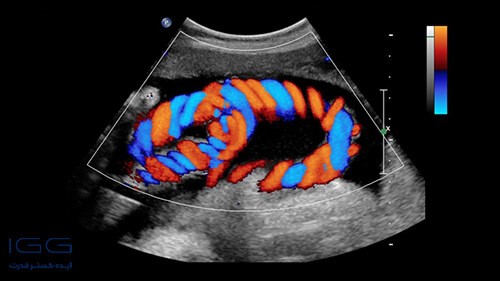

سونوگرافی کالر داپلر در بارداری

انجام سونوگرافی کالر داپلر در دوران بارداری بسیار ساده است. در این روش لازم است ابتدا شخص روی تخت دراز بکشد. سپس پروب دستگاه در مقابل سطح پوست قرار میگیرد و امواج صوتی به سمت اندامهای داخلی بدن مثل تخمدان و رحم تابیده میشوند. امواج سونوگرافی داپلر بعد از برخورد با رگهای خونی بازتاب شده و تصاویر جریان خون متحرک را روی صفحه نمایشگر نشان میدهند. با این تفاوت که جریان خون بدن به شکل رنگی مشاهده میشود.

بنابراین، اپراتور سونوگرافی یا پزشک متخصص به راحتی میتواند میزان رشد جنین و نواقص مادرزادی را مورد بررسی قرار دهد. تشخیص سرعت و نوع حرکت جریان خون به کمک سونوگرافی کالر داپلر، باعث میشود تا امکان بررسی دقیقتر جنین فراهم باشد. بنابراین پیشنهاد میشود همه مادران باردار برای انجام سونوگرافی کالر داپلر در دوران حاملگی اقدام کنند. گاهی اوقات ممکن است اپراتور سونوگرافی یک ژل مخصوص را روی سطح پوست قرار دهد تا امواج به راحتی به داخل اندامهای داخلی بدن تابیده شده و به سرعت بازتاب شوند. همچنین در برخی از مواقع لازم است تکنسین، پروب دستگاه را روی سطح پوست فشار دهد که ممکن است کمی ناراحت کننده باشد. ولی به سرعت درد آن از بین خواهد رفت. سونوگرافی کالر داپلر معمولا بین ۳۰ تا ۴۰ دقیقه طول میکشد. اما اگر نیاز به اسکن کردن باشد، ممکن است مدت زمان انجام سونوگرافی کالر داپلر افزایش پیدا کند.